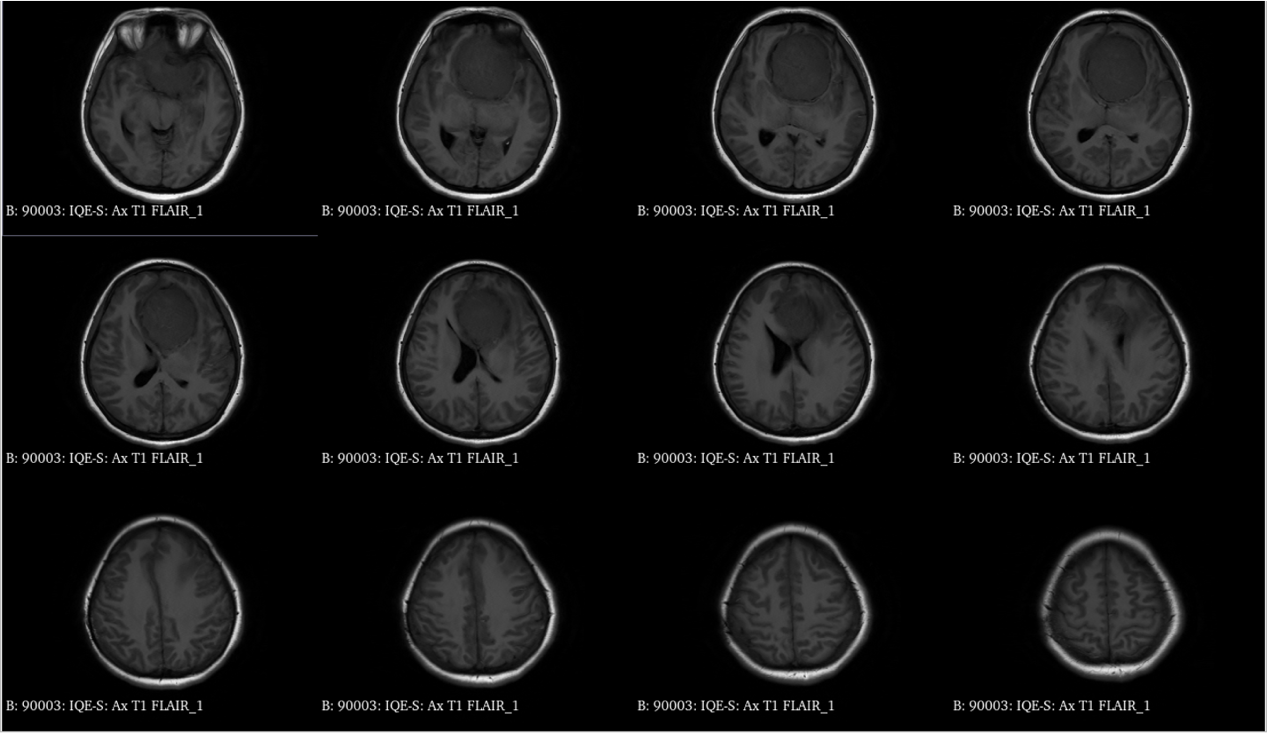

青年女性,因“左眼失明10个月,头痛3个月”就诊我院。

入院诊断:颅内占位病变(前颅窝底)脑膜瘤?;左眼失明;鼻炎

前颅窝底脑膜瘤常起源于前颅底筛骨筛板处的硬膜,瘤体多为双侧生长,少数为偏侧生长,女性稍多于男性。肿瘤可累及鸡冠和蝶骨平台的任何区域,是前颅窝肿瘤中最多见的一种。因为肿瘤位于前颅窝底,额叶在功能上属于“哑区”,患者就诊发现肿瘤时瘤体多已巨大。主要症状可有颅内压增高症状、视力减退、癫痫以及精神症状等。该患者主因“左眼失明10个月,头痛3个月”就诊。术中采用双额冠状开颅,左侧为主,由于肿瘤体积巨大,术中切除少许薄层额叶脑组织,边离断基底、边瘤内减压,分块切除肿瘤,最终探查肿瘤基底主要位于鸡冠、筛板、蝶骨平台、鞍结节、前床突处硬膜,术中见肿瘤供血主要来源于前颅窝底硬膜及大脑前动脉分支,术中仔细辨认供血动脉、过路血管,大脑前动脉及其分支保护完好,术中见视神经、视交叉受压明显,尤其是左侧视神经已缺血苍白,最终达Simpson II级切除。术者体会,该患者术前行多模态重建,可见瘤表数条粗大的静脉,术中切莫过早离断肿瘤的引流静脉,以防因引流不畅致瘤体肿胀出血;术前行多模态重建,利于鉴别供血动脉、过路血管,早期离断供血动脉更利于肿瘤切除;该类肿瘤基底一般较为广泛,不能盲目离断基底,尤其是近鞍结节处,可以于中线处离断基底,进入第一间隙后向两侧探查并保护视神经,待充分缩小瘤体看清楚毗邻的血管神经后再将其完全切除;术毕做好多层颅底重建以防脑脊液漏。另外,该患者术前左眼失明已达10个月,术后第1天即有光感,术后1月复查左眼视力可达50cm内数指,这在临床中非常少见,对于此类病人,不要轻易放弃挽救视力的任何机会。